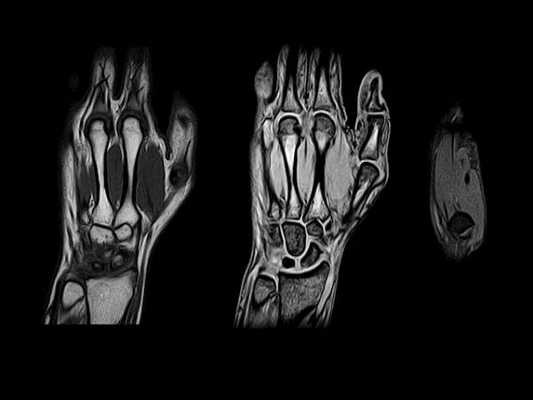

(Слева) На фронтальной МРТ GRE определяется центральная перфорация треугольного фиброзно-хрящевого комплекса и потеря хряща головки локтевой кости и проксимальной поверхности полулунной кости с кистозными изменениями. Полулунно-трехгранная связка интактная. Полулунная кость II типа.

(Справа) На фронтальной МРТ в режиме STIR определяется типичная картина импичмента шиловидного отростка локтевой кости с отеком в шиловидном отростке локтевой кости и по периферии трехгранной кости и синдрома легкого сдавливания локтевой кости. Имеется синовит в прешиловидных мягких тканях.